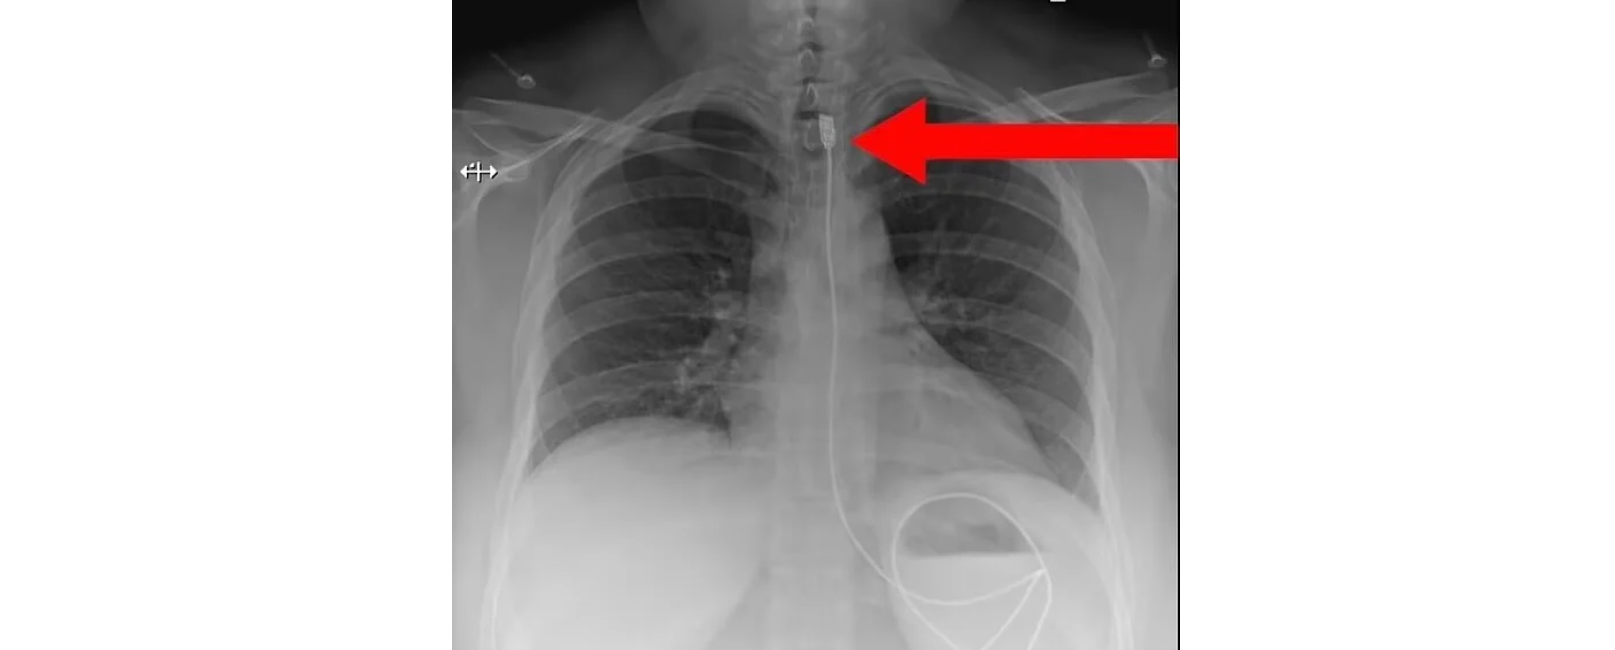

Γυναίκα που πάσχει από μια σπάνια διατροφική διαταραχή χρειάστηκε να υποβληθεί σε επείγουσα χειρουργική επέμβαση αφού προσπάθησε να καταπιεί ένα καλώδιο φορτιστή iPhone μήκους σχεδόν ενός μέτρου.

Η γυναίκα από την Πολωνία φέρεται να πάσχει από Pica, διαταραχή που συνδέεται με την κατανάλωση μη φαγώσιμων ουσιών.

Μεταφέρθηκε εσπευσμένα στο χειρουργείο αφού το καλώδιο σφηνώθηκε στον οισοφάγο της.

Καλώντας τις υπηρεσίες έκτακτης ανάγκης αφού άρχισε να ασφυκτιά, η γυναίκα φέρεται να έλαβε επείγουσα θεραπεία για την αφαίρεση του καλωδίου, σύμφωνα με την Daily Mail.

Δημοσιεύοντας μια ακτινογραφία στο Facebook, μια ομάδα με την ονομασία «Ready to Rescue» που κάνει μαθήματα Πρώτων Βοηθειών στην πολωνική πόλη Wroclaw ανέφερε:

Η φωτογραφία δημοσιεύτηκε αρχικά στη σελίδα στα social media μιας ομάδας που αυτοαποκαλείται Savage Paramedics, η οποία περιγράφει τον εαυτό της ως «μια κοινότητα για επαγγελματίες υγείας που συναντιούνται για χιούμορ, διασκέδαση και εκπαίδευση», και πρωτοεμφανίστηκε το Σάββατο.

Συνοδευόταν από μια άλλη φωτογραφία που έδειχνε σε κοντινό πλάνο τον φορτιστή του τηλεφώνου που είχε σφηνωθεί μέσα στο λαιμό της γυναίκας.

«Το καλώδιο αφαιρέθηκε με επιτυχία στο νοσοκομείο και η γυναίκα ανάρρωσε πλήρως. Ωστόσο δεν είπε σε κανέναν τον λόγο για τον οποίο κατάπιε αρχικά το καλώδιο φόρτισης. Καμία ιδέα;», ανέφερε η ομάδα.